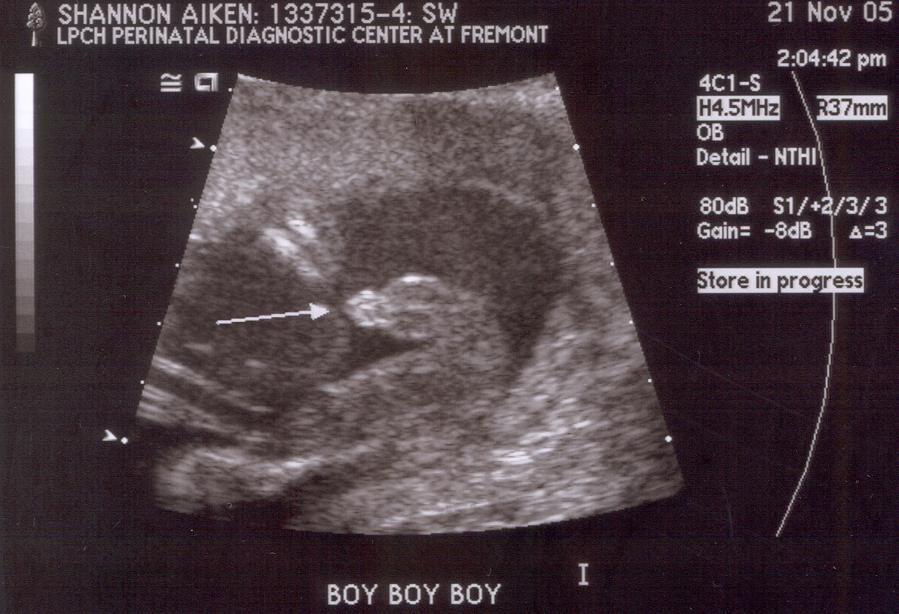

20 weeks: